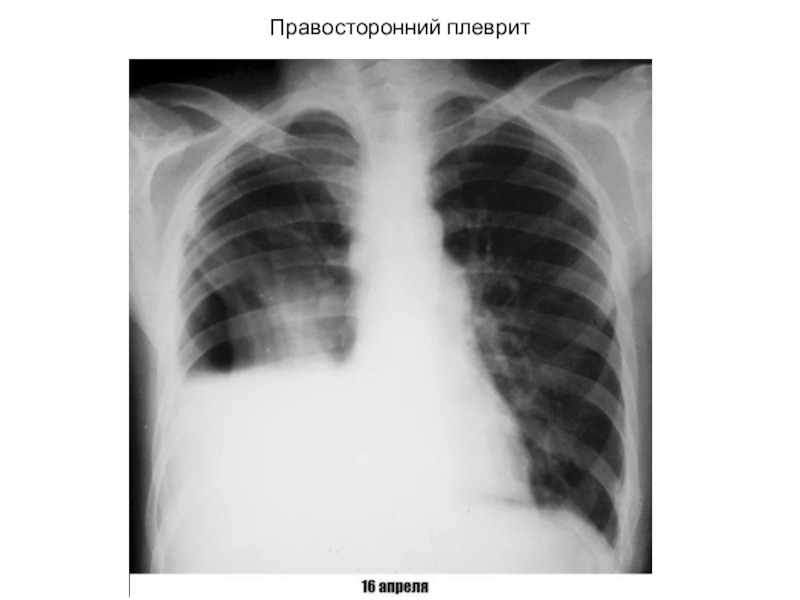

Слайд 61Правосторонний плеврит

Правосторонний плеврит